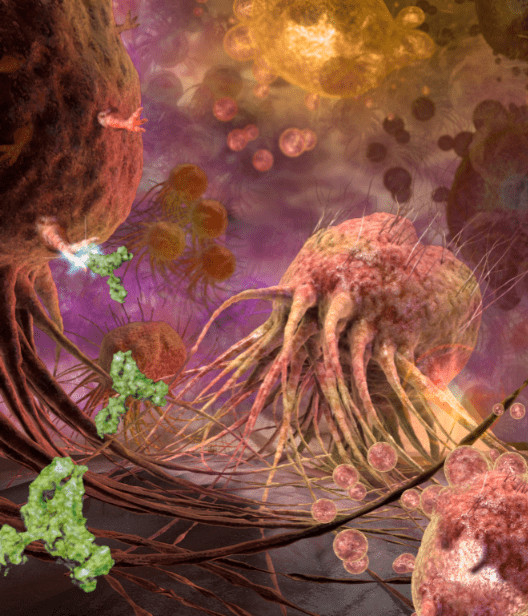

Illustration Honorable Mention – Tumor Death

This illustration shows tumor death-cell receptors on breast cancer cell surfaces targeted by the monoclonal antibody TRA-8, which was developed at the University of Alabama, Birmingham School of Medicine.